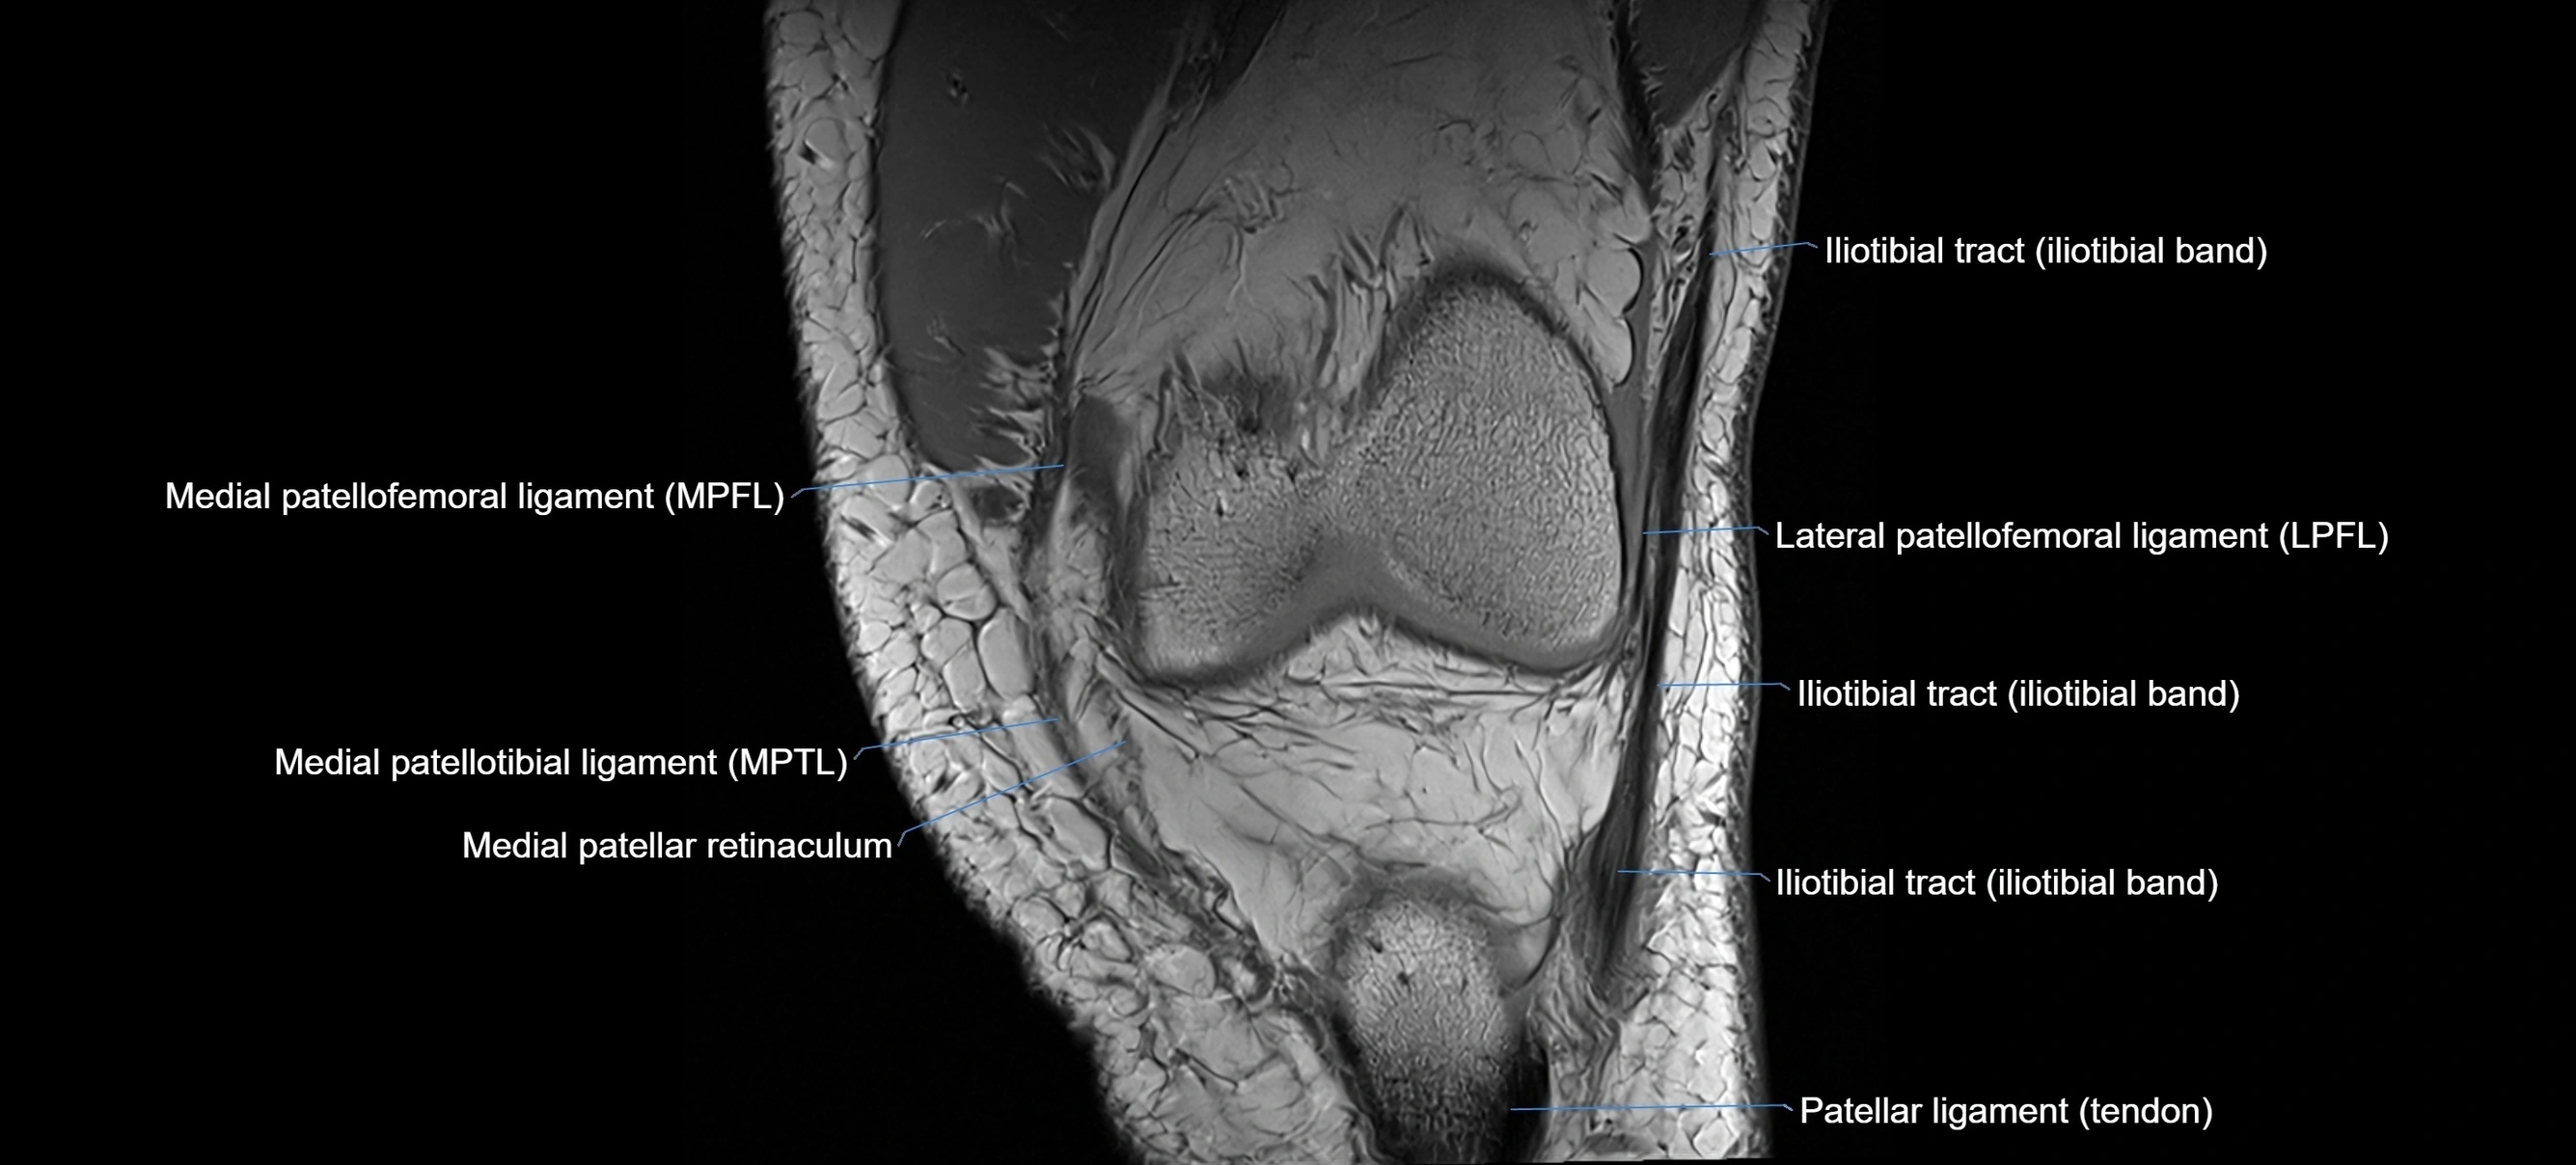

MRI images

image